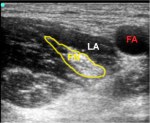

- Femoral Nerve Block – LA=local anesthetic surrounding the femoral nerve